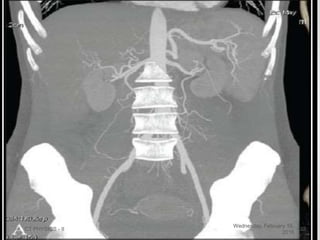

CT ANGIO

• Utilises the principle of using

narrow collimation to scan the

region and reconstructing both

thin and thick slices .

• Superior quality tomographic

images .

• The high resolution slices allow

luminal views of the vessel . (“fly

through”)

CT ANGIO • Utilisesthe principle of using narrow collimation to scan the region and reconstructing both thin and thick slices . • Superior quality tomographic images . • The high resolution slices allow luminal views of the vessel . (“fly through”) Wednesday, February 10, 2016 CT PHYSICS - II 28